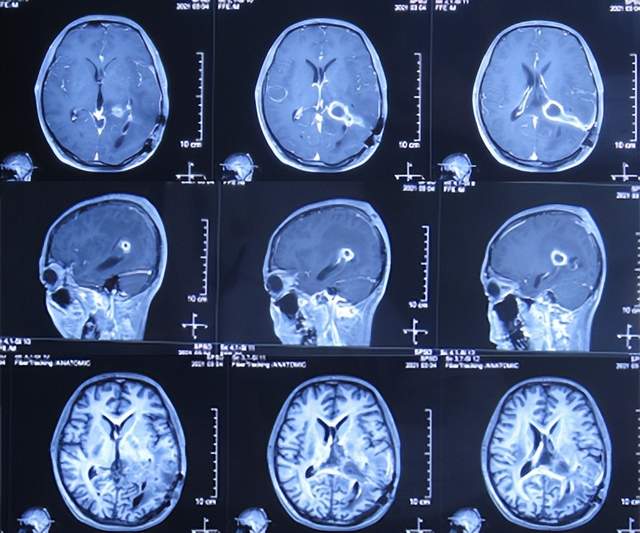

直到2021年1月8日(间断头痛4年后),因无法忍受头痛,就诊于山东省济南市商河某医院,查头颅核磁示颅内占位(图-1)。

图-1:2021年1月8日头颅核磁

为治疗脑瘤,于5天后即2021年1月13日,就诊于山东省某省级三甲医院,查头颅核磁增强(图-2)和头颅血管造影(图-3)示颅内占位。

图-2:2021年1月13日头颅核磁增强

图-3:2021年1月13日头颅血管造影

入院后5天即2021年1月18日,查头颅CT增强示颅内占位(图-4)。

图-4:2021年1月18日头颅CT增强